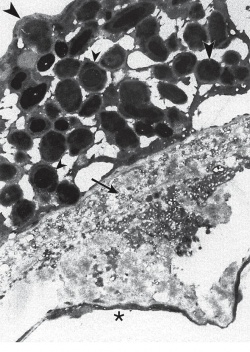

Pattern dystrophy is caused by lipofuscin accumulation in the RPE layer of the retina. Light and transmission electron microscopic examination shows loss of the RPE and photoreceptor cell layer, with intact choriocapillaris and lipofuscin-containing cells in the sub-retinal space in the macula. [2]

Little is known about the pathophysiology of the various pattern dystrophies. However reports have shown multiple cysteine mutations within the PRPH2 gene. The disulfide bond within proteins is believed to be held by cysteine and any interruption of that could disrupt the integrity of the photoreceptor disc membrane. This can lead to degeneration of photoreceptor cells and ultimately results in an accumulation of lipofuscin in the RPE.[2] [14]